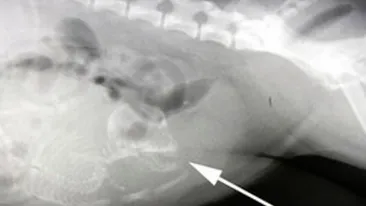

CUTREMURĂTOR! Cum s-a născut această copilă, pentru ca mama ei a consumat droguri in timpul sarcinii! Imagini greu de privit